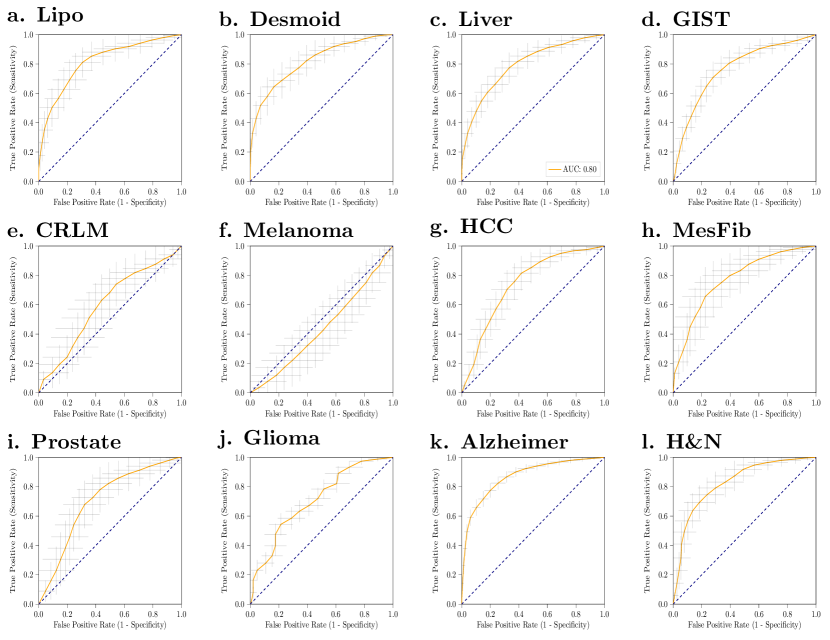

Error plots of the AUC from the application of our WORC framework with the same default configuration on the twelve different datasets are shown in Figure 3; detailed performances, including other metrics, are shown in Table 3; the ROC curves are shown in Figure A.2. In eleven of the twelve datasets, we successfully found a prediction model, with mean AUCs of 0.83 (Lipo), 0.82 (Desmoid), 0.80 (Liver), 0.77 (GIST), 0.61 (CRLM), 0.75 (HCC), 0.80 (MesFib), 0.72 (Prostate), 0.71 (Glioma), 0.87 (Alzheimer), and 0.84 (H&N). In the Melanoma dataset, the mean AUC (0.45) was similar to that of guessing (0.50).

| Dataset | Lipox | Desmoidx | Liverx | GISTx | CRLMx | Melanomax |

|---|---|---|---|---|---|---|

| AUC | 0.83 [0.76, 0.90] | 0.82 [0.75, 0.89] | 0.80 [0.74, 0.86] | 0.77 [0.71, 0.83] | 0.61 [0.49, 0.75] | 0.45 [0.34, 0.57] |

| BCR | 0.74 [0.66, 0.82] | 0.74 [0.66, 0.81] | 0.72 [0.65, 0.78] | 0.71 [0.65, 0.77] | 0.59 [0.48, 0.71] | 0.47 [0.38, 0.56] |

| 0.74 [0.65, 0.82] | 0.77 [0.70, 0.83] | 0.72 [0.65, 0.78] | 0.71 [0.65, 0.77] | 0.58 [0.46, 0.70] | 0.44 [0.35, 0.54] | |

| Sensitivity | 0.69 [0.56, 0.83] | 0.75 [0.43, 0.70] | 0.71 [0.61, 0.82] | 0.68 [0.57, 0.79] | 0.58 [0.39, 0.76] | 0.58 [0.42, 0.75] |

| Specificity | 0.79 [0.68, 0.90] | 0.90 [0.83, 0.96] | 0.72 [0.62, 0.82] | 0.75 [0.66, 0.83] | 0.61 [0.42, 0.79] | 0.35 [0.19, 0.51] |

| Dataset | HCCx | MesFibx | Prostatex | Gliomab | Alzheimerx | H&Nx |

| AUC | 0.75 [0.67, 0.82] | 0.80 [0.68, 0.92] | 0.72 [0.61, 0.82] | 0.71 [0.61, 0.80] | 0.87 [0.84, 0.90] | 0.84 [0.76, 0.92] |

| BCR | 0.69 [0.62, 0.77] | 0.71 [0.59, 0.83] | 0.67 [0.57, 0.78] | 0.65 [0.57, 0.73] | 0.78 [0.75, 0.81] | 0.74 [0.66, 0.82] |

| 0.69 [0.62, 0.76] | 0.70 [0.58, 0.82] | 0.67 [0.56, 0.78] | 0.61 [0.52, 0.69] | 0.80 [0.77, 0.83] | 0.74 [0.66, 0.82] | |

| Sensitivity | 0.73 [0.59, 0.86] | 0.74 [0.56, 0.91] | 0.67 [0.49, 0.85] | 0.49 [0.38, 0.59] | 0.69 [0.64, 0.75] | 0.80 [0.69, 0.91] |

| Specificity | 0.66 [0.55, 0.78] | 0.68 [0.50, 0.86] | 0.68 [0.53, 0.82] | 0.82 [0.71, 0.93] | 0.87 [0.83, 0.90] | 0.68 [0.56, 0.80] |